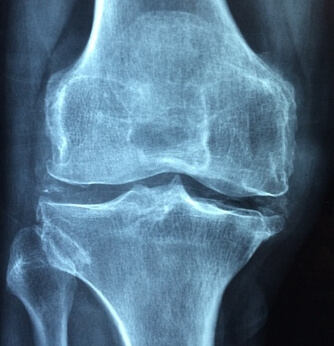

그럼, 관절염을 예방하기 위해서 먼저 관절염의 다양한 원인에 대해서 알아볼 필요가 있겠습니다. 관절염은 하나 이상의 관절사이에 염증이 발생하여 통증과 움직이는 기능이 어려워지는 것을 일반적으로 이야기합니다.

관절염은 일반적으로 나이가 들수록 증가하게 되는데요. 이는 관절이 시간이 지남에 따라서 마모되고 손상되기 쉽고, 예상치 못한 손상으로 인해 다양한 유형의 관절염이 발생하게 됩니다.

과격한 활동을 하거나 사고등으로 신체의 관절이 골절되거나 탈구와 같은 부상을 당하면 이로 인해서 이후에 관절에 염증이 발생할 위험이 증가하게 됩니다, 관절의 부상은 관절의 구조를 변화시키기 때문에 결과적으로 관절염을 유발할 가능성이 많습니다.